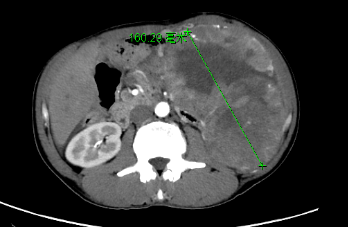

张大叔最近出现腹胀不适等症状,就诊于国内多家医院,均被告知腹腔肿块巨大,曾经做了小肠间质瘤切除术,腹腔粘连严重,手术风险极大,术中术后大出血、肺部感染、吻合口漏、呼吸衰竭、心脑血管意外等,多次告知患者失去手术机会,回家休养。患者每日寝食难安、坐卧不安、失眠、吃不下饭,每晚抱着几十斤瘤子睡觉,对生活失去了信心。后患者在家人鼓励下,慕名找到我院涂从银主任。

涂主任仔细询问病情,反复看腹部CT等检查,表示此瘤子可治。张大叔及家人瞬间泪目,“您是我们的救命恩人”,张大叔激动地说。经过全科医护人员讨论,研究方案,怎样减少并发症。2月22日,在麻醉科的全力配合下,涂主任带领团队为张大叔做了腹膜后肿瘤切除+肠粘膜松解术+左半结肠切除+直肠切除+小肠肠段切除术。术后,张大叔恢复情况较好。(综合外科 陈琳 文/图)